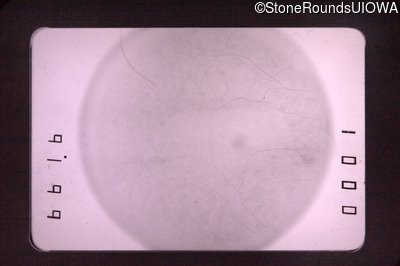

Fluorescein Angiography - Right - 20/30

Exemplar